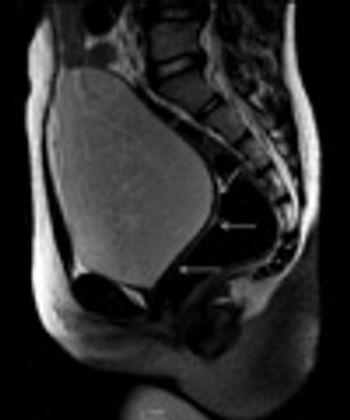

Male Pseudohermaphroditism

A 15-year-old female patient with primary amenorrhea and absent secondary sexual characters.